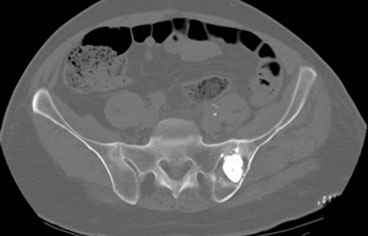

Bu yöntem hassas ve ağrılı bir işlem olduğu için görüntüleme eşliğinde (sıklıkla tomografi (özellikle osteoid osteoma uygulamalarında) nadiren floroskopi dediğimiz portabl röntgen eşliğinde) ve anestezi altında (lokal değil spinal/epidural ya da genel anestezi) uygulanmaktadır.

Özellikle kalça çevresi ve uyluk gibi derin yerleşimli osteoid osteoma vakalarında açık cerrahi ile tümörün tespiti zor olabileceği için atlama riski vardır. Ayrıca açık cerrahi ile yara problemi ve kemikte oluşacak harabiyete bağlı kırık riski yüksektir. Osteoid osteoma da RF ablasyon işlemi tomografi altında yapılacağı için atlanma riski yok denecek kadar azdır ve kapalı bir işlem olduğundan (<1cm) yara sorunu son derece nadirdir.

Elektrotun osteoid osteomada nidusa en yakın yere diğer iyi huylu tümörlerde ise tümörün merkezine yerleştirilmesi işlemin etkisi ve tedaviye yanıtı açısından son derece önemlidir. İşlem esnasında ısı kademeli olarak 90 dereceye kadar artırılıp 6-7 dakika süreyle yakma işlemi gerçekleştirildikten sonra tekrar kademeli olarak düşürülür.